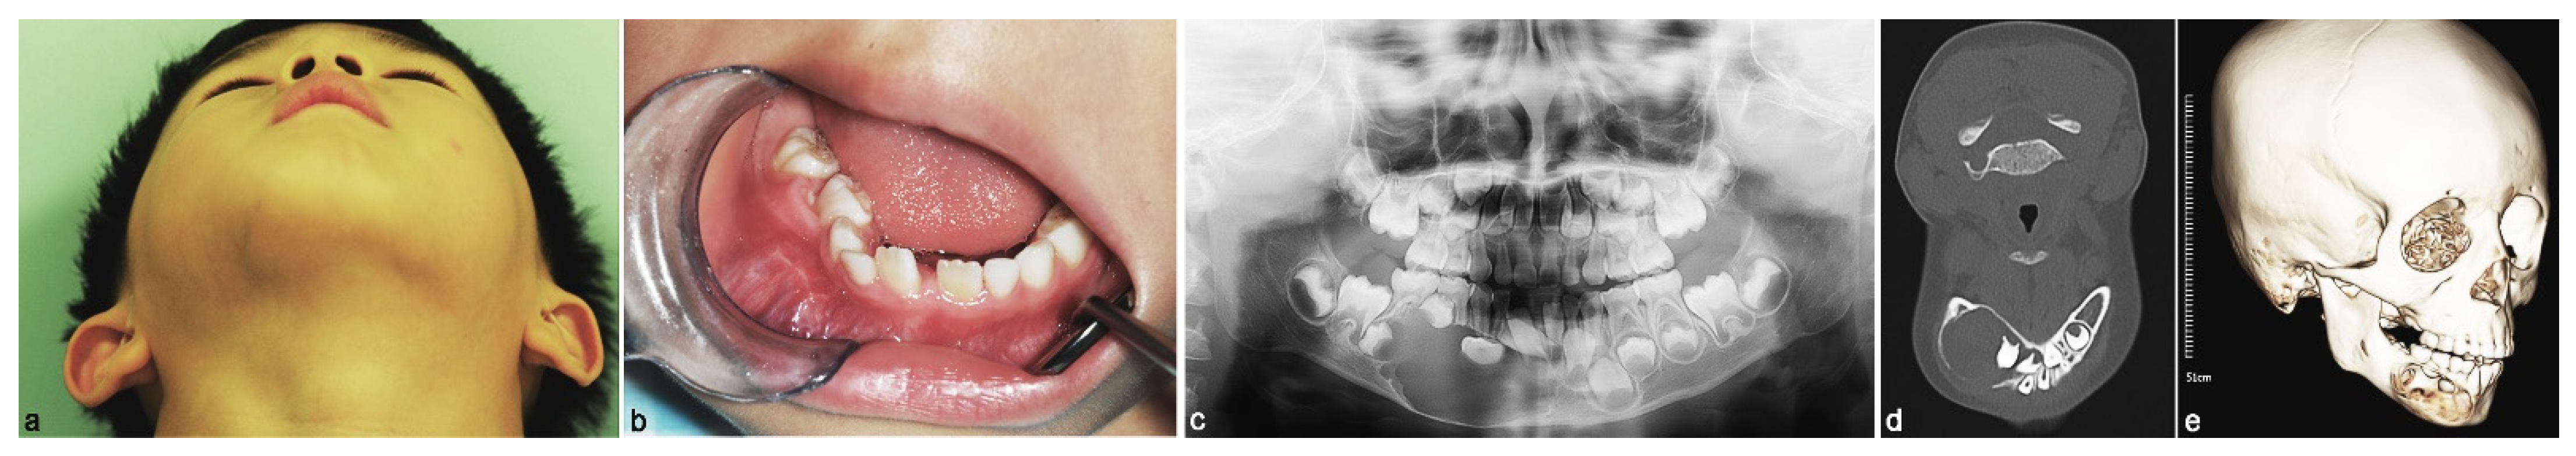

2. Case Report